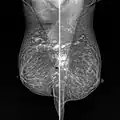

Snowball like hyperechogenic axillary lymph nodes in a woman with silicone implants removed due to complications | |